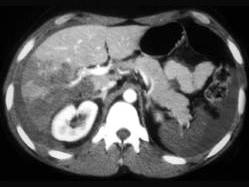

问题 下列图像最佳诊断是 ( )

选项 A、小肠破裂 B、胰腺损伤 C、结肠破裂 D、肝破裂 E、脾破裂

答案 D